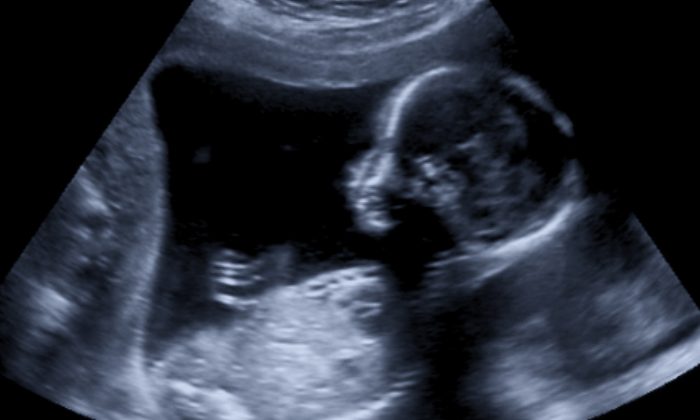

「この子は果たして『普通の人間』となれるのか」超音波検査の結果は、どんな苦境においても必ず希望はあると思えない程に医師には衝撃的でした。

しかし、その検査で予想外過ぎる衝撃的な事実に直面。男の子の赤ちゃんに、脳が額から突出した非常に稀な鼻脳ヘルニアが見つかったのです。

成長するにつれそのヘルニアが巨大になるため、この子が普通の「人間」としては育たないであろうことを医師に告げられ、すぐに堕胎するよう勧められます。